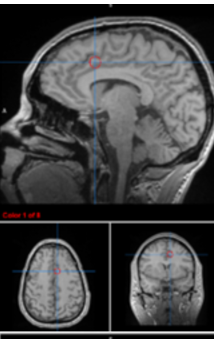

hippocampus

memory consolidation